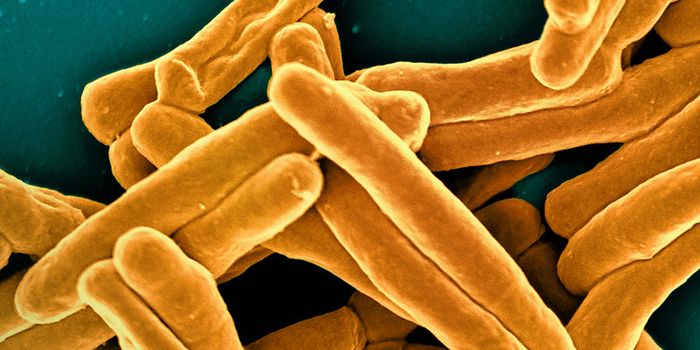

FEB 16, 2025MicrobiologyBacterial pathogens can cause serious infections. So many of them are becoming resistant to the effects of antibiotics t ...

FEB 05, 2025MicrobiologyAntibiotics are a crucial tool in the fight against bacterial infections. But the World Health Organization has long war ...

DEC 08, 2024Clinical & Molecular DXA rapid diagnostic test for tuberculosis (TB) has been approved for the first time by the World Health Organization (WHO ...